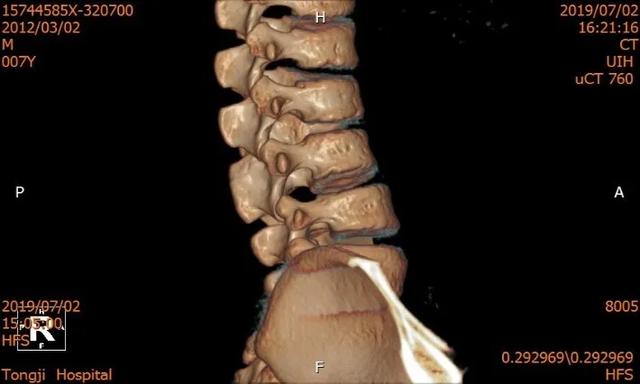

术前正位

术前侧位